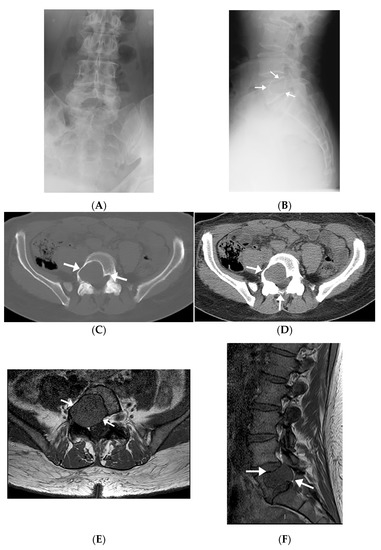

3.1.2. Radiographic Imaging

Radiographs were available on four patients. One of these only had a postoperative radiograph in which the lesion was occult. Other radiographs demonstrated geographic lytic lesions with sclerotic borders (Figure 2A,B).

Figure 2.

Radiographic, MR, and CT imaging appearances of intraosseous schwannoma in a 57-year-old man involving the L5 vertebral body and invading right L5 neural foramen. (A,B) The mass is occult on an AP radiograph (A), but the lateral radiograph (B) shows a large lobular lytic lesion with sclerotic margins. (C,D) Axial CT images in bone (C) and soft tissue (D) windows show an expansile lytic lesion in the right aspect of the L5 vertebral body extending into the pedicle and encroaching upon the right neural foramen and right lateral recess (arrows). (E,F) The mass extends into the right pedicle, encroaching upon the right neural foramen and right lateral recess and has a similar-to-slightly-lower signal relative to the muscle on axial (E) and sagittal (F) T1-weighted images (arrows).

3.1.3. Computed Tomography

All patients had CT images available. Four patients underwent diagnostic CT studies, while the other two had preprocedural CT images obtained during the CT-guided biopsy. Imaging findings mostly included expansile intraosseous lytic lesions extending into adjacent spaces, including the neuroforamina, epidural space, and central spinal canal (Figure 2C,D). There was one case of a locally aggressive tumor extending anteriorly into the pelvis and posteriorly into the epidural space (Figure 3). The masses were characterized on imaging as heterogeneous, expansile lesions with centrally hypodense areas and peripheral rims of sclerosis.

3.1.4. Magnetic Resonance Imaging

All IOSs demonstrated consistent signal characteristics on MRI with a low-to-intermediate signal intensity to muscle on T1-weighted images (T1-WI) and heterogenous hyperintense signal intensity on fluid-sensitive sequences. Extra-osseous extension was frequently demonstrated, including invasion into neural foramina with displacement of adjacent nerve roots (Figure 2E,F) and involvement of the epidural space. There was posterior osseous extension from vertebral bodies into the pedicles and spinous processes. There was avid post-contrast enhancement with scattered areas of central non-enhancement.